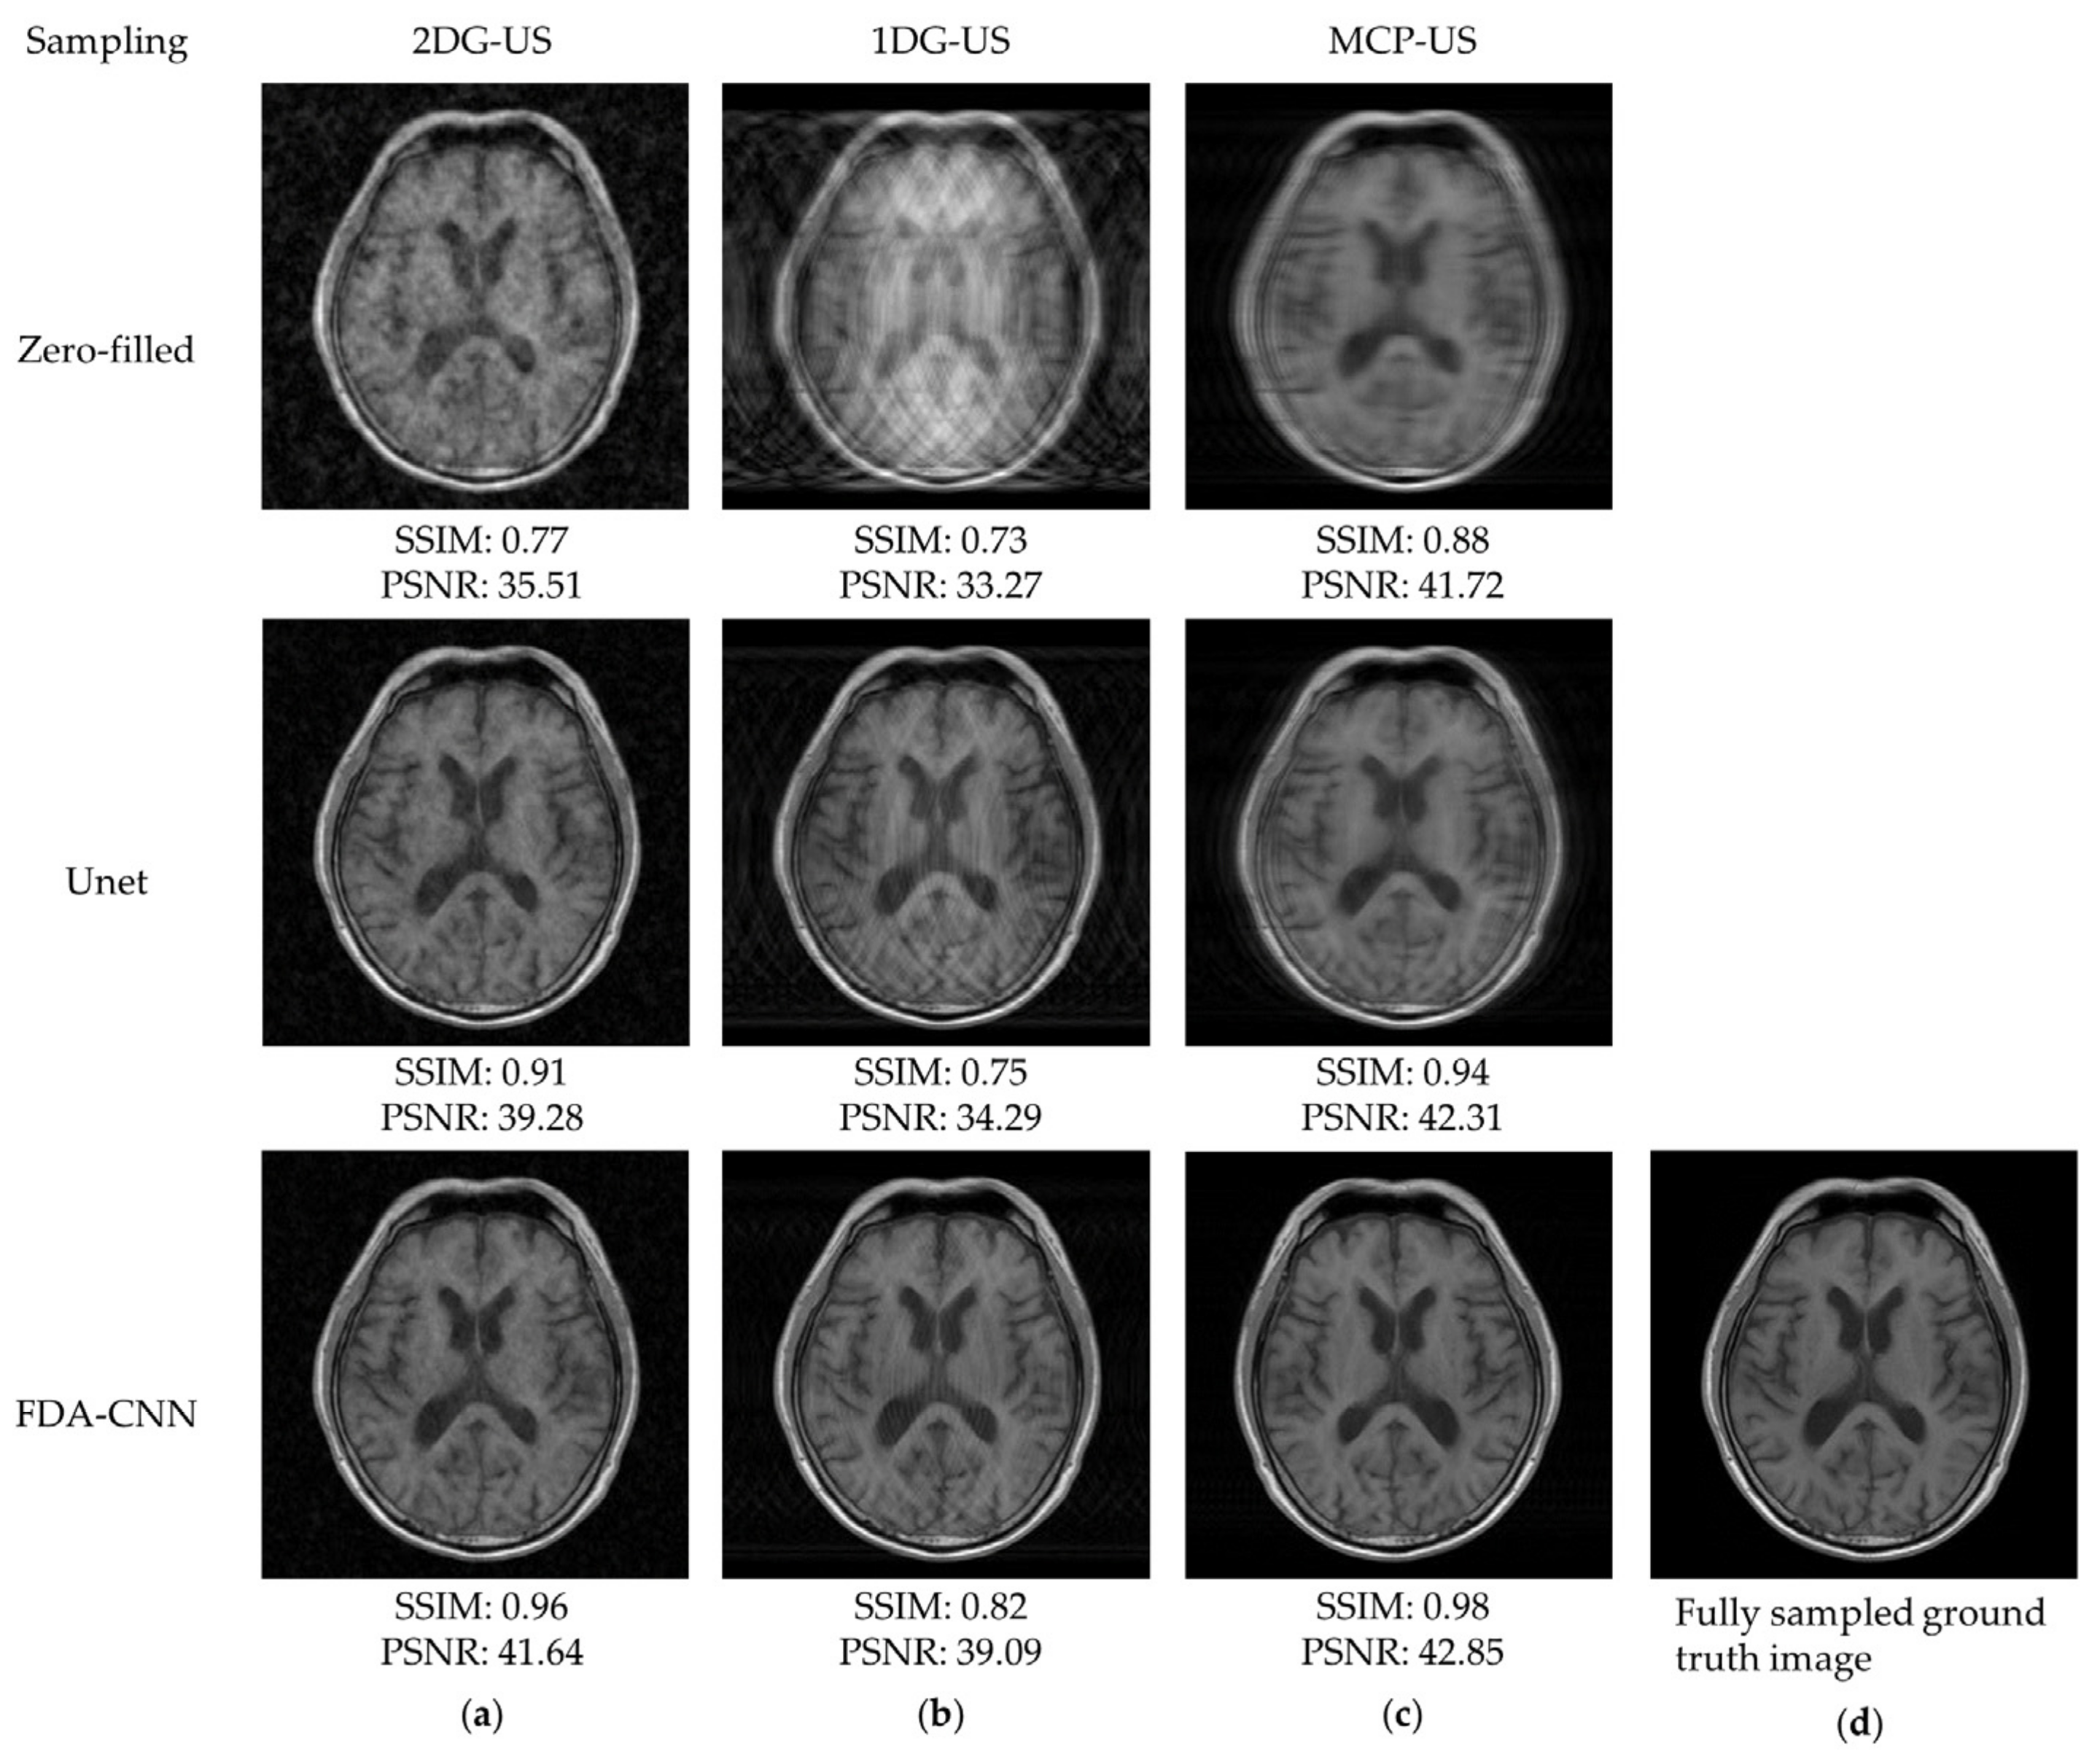

4.2. FastMRI and IXI Datasets